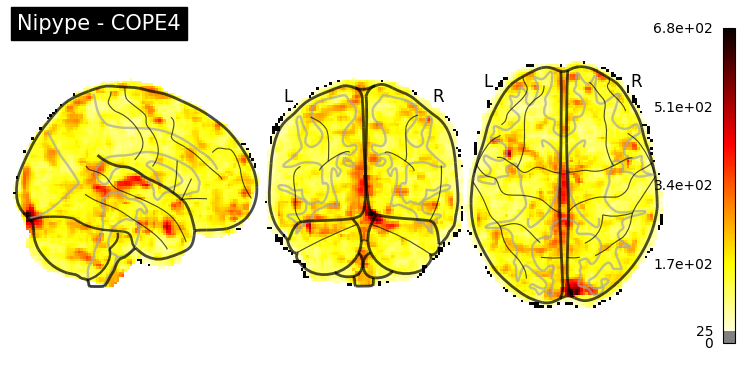

The first-level GLM#

Here we randomly choose the four copes from subject-09 run-1

plotting.plot_stat_map(nipype_cope1, bg_img=nipype_cope1, title = 'Nipype - COPE1', cmap = 'bwr', colorbar = False)

plt.show()

plotting.plot_stat_map(nipype_cope2, bg_img=nipype_cope1, title = 'Nipype - COPE2', cmap = 'bwr', colorbar = False)

plotting.plot_stat_map(nipype_cope3, bg_img=nipype_cope1, title = 'Nipype - COPE3', cmap = 'bwr', colorbar = False)

plotting.plot_stat_map(nipype_cope4, bg_img=nipype_cope1, title = 'Nipype - COPE4', cmap = 'bwr', colorbar = False)

../../_images/a7f7f387884673a96e62aa7d2d938a6b6487846759bc4500b6d0cff677c7358d.png ../../_images/bc743ce13891ebab23c9f6c7d4d668db8d11c9409d4f6e4580f7d63b35ecdb77.png ../../_images/228b3b22c00177a8ad5dc1793cbbc90dbfb495735196a4af47e73b899de0ca82.png ../../_images/babe8f68f0856f0f1608dfe550483d8ca862aae33a659d1f970a9fbe726f3bb1.png